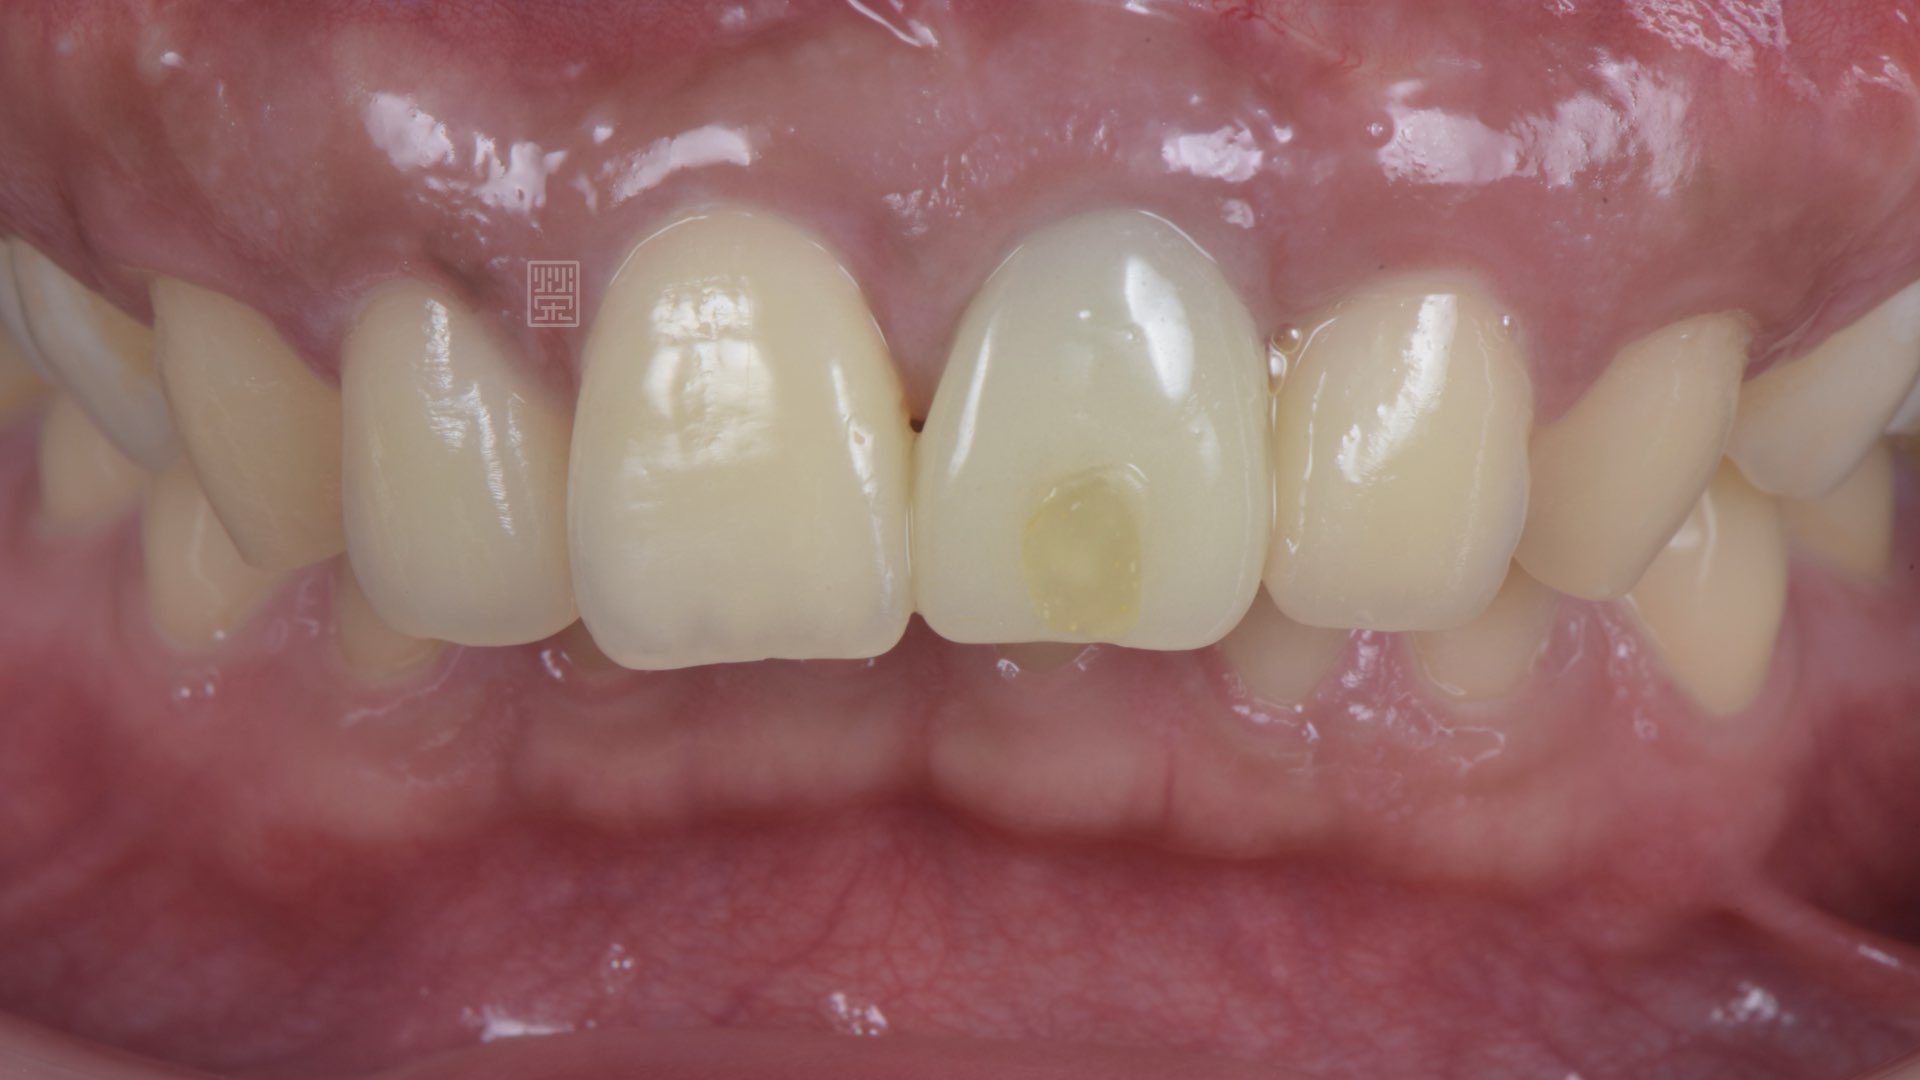

植牙全瓷冠

植牙完成